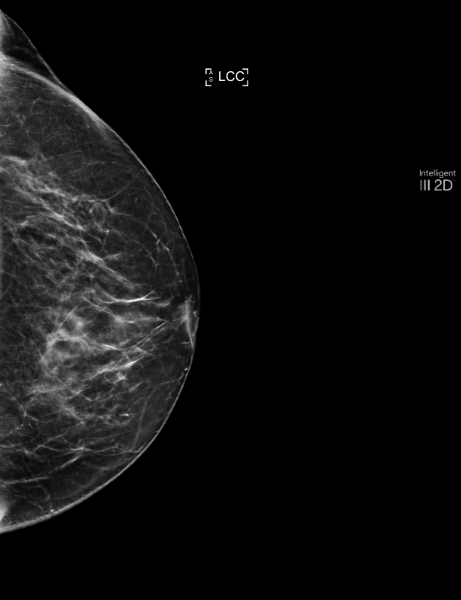

By analyzing the previous 2022 review with MammoScreen, the mass, still smaller and less spiced, is detected by the software with a score of 5 on both incidences.